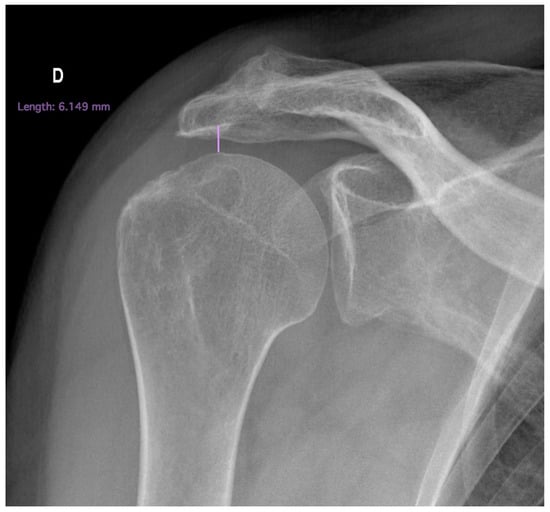

- Acromiohumeral distance